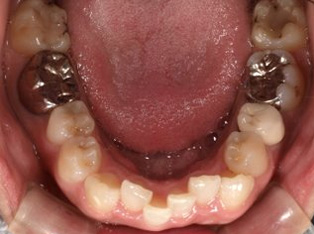

乱ぐい歯、でこぼこがとても酷い状態になります。歯が前後的に重なってしまっている、八重歯になっているなどがこのジャンルに入ります。

顎の大きさと歯の大きさのギャップが大きく、時には歯を抜かないと矯正治療ができない場合もあります。当院では治療期間が長くなるが抜かない治療方針など、一つの治療プランだけでなく、さまざまな可能性の治療方針を説明させて頂くよう心掛けております。こういった考え方はインフォームド・チョイスと言われ近年大切にされている考え方と言われております。

治療前

治療終了前